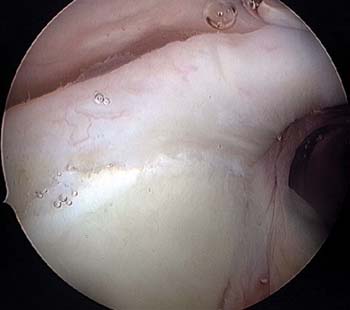

La clasificación original y mas comúnmente utilizada es

la clasificación descripta por Snyder y col.2,6,7en 1990 basadas en hallazgos artroscópicos de las lesiones del labrum superior (Figura 1); clasificando la lesión SLAP en 4 tipos donde el tipo I es una abrasión o deflecamiento del labrum superior sin evidenciar inestabilidad de la unidad funcional bíceps labrum; la desinserción del labrum superior que compromete la inserción y la estabilidad de la porción larga del bíceps es la lesión tipo II, es importante reconocer la inserción meniscoide (Figura 2) del labrum superior y su inserción medial en la glena, como una variante anatómica normal que no debe ser confundida con una desinserción del labrum superior. La desinserción del labrum superior en asa de balde que no compromete la estabilidad de la inserción del bíceps, es la lesión SLAP tipo III, pero puede producir síntomas mecánicos; y la lesión en asa de balde que se extiende a la porción larga del bíceps, es la lesión SLAP tipo IV. Luego de la clasificación de Snyder y col.2,6,7 se incorporaron otras clasificaciones para incluir lesiones más complejas que no habían sido incorporadas en la clasificación original. Maffet y col.,43 en 1995, expandieron la clasificación de Snyder describiendo como lesión SLAP tipo V a la continuación de la lesión SLAP II con una lesión de Bankart, la lesión tipo VI es la lesión SLAP tipo II combinada con un flap en la base del bíceps y la lesión SLAP tipo VII es la lesión SLAP tipo II que se extiende al ligamento glenohumeral medio. Posteriormente Morgan et al.21 subdividen la lesión tipo II en tres subtipos, lesión tipo II anterior, posterior y combinada anterior y posterior; este articulo fue significativo para entender el mecanismo de la lesión SLAP tipo II y la importancia clínica de esta subdivisión es que demostraron que las lesiones tipo II que se extienden a posterior, son las que en el tiempo pueden evolucionar a una lesión parcial profunda del manguito rotador, recomendando la reparación con arpones.13,15,19,21

Figura 1: Clasificación SLAP, Snyder. Visualización Artroscópica: A: Tipo I B: Tipo II C: Tipo III D: Tipo IV.

Figura 2: Inserción Meniscoides